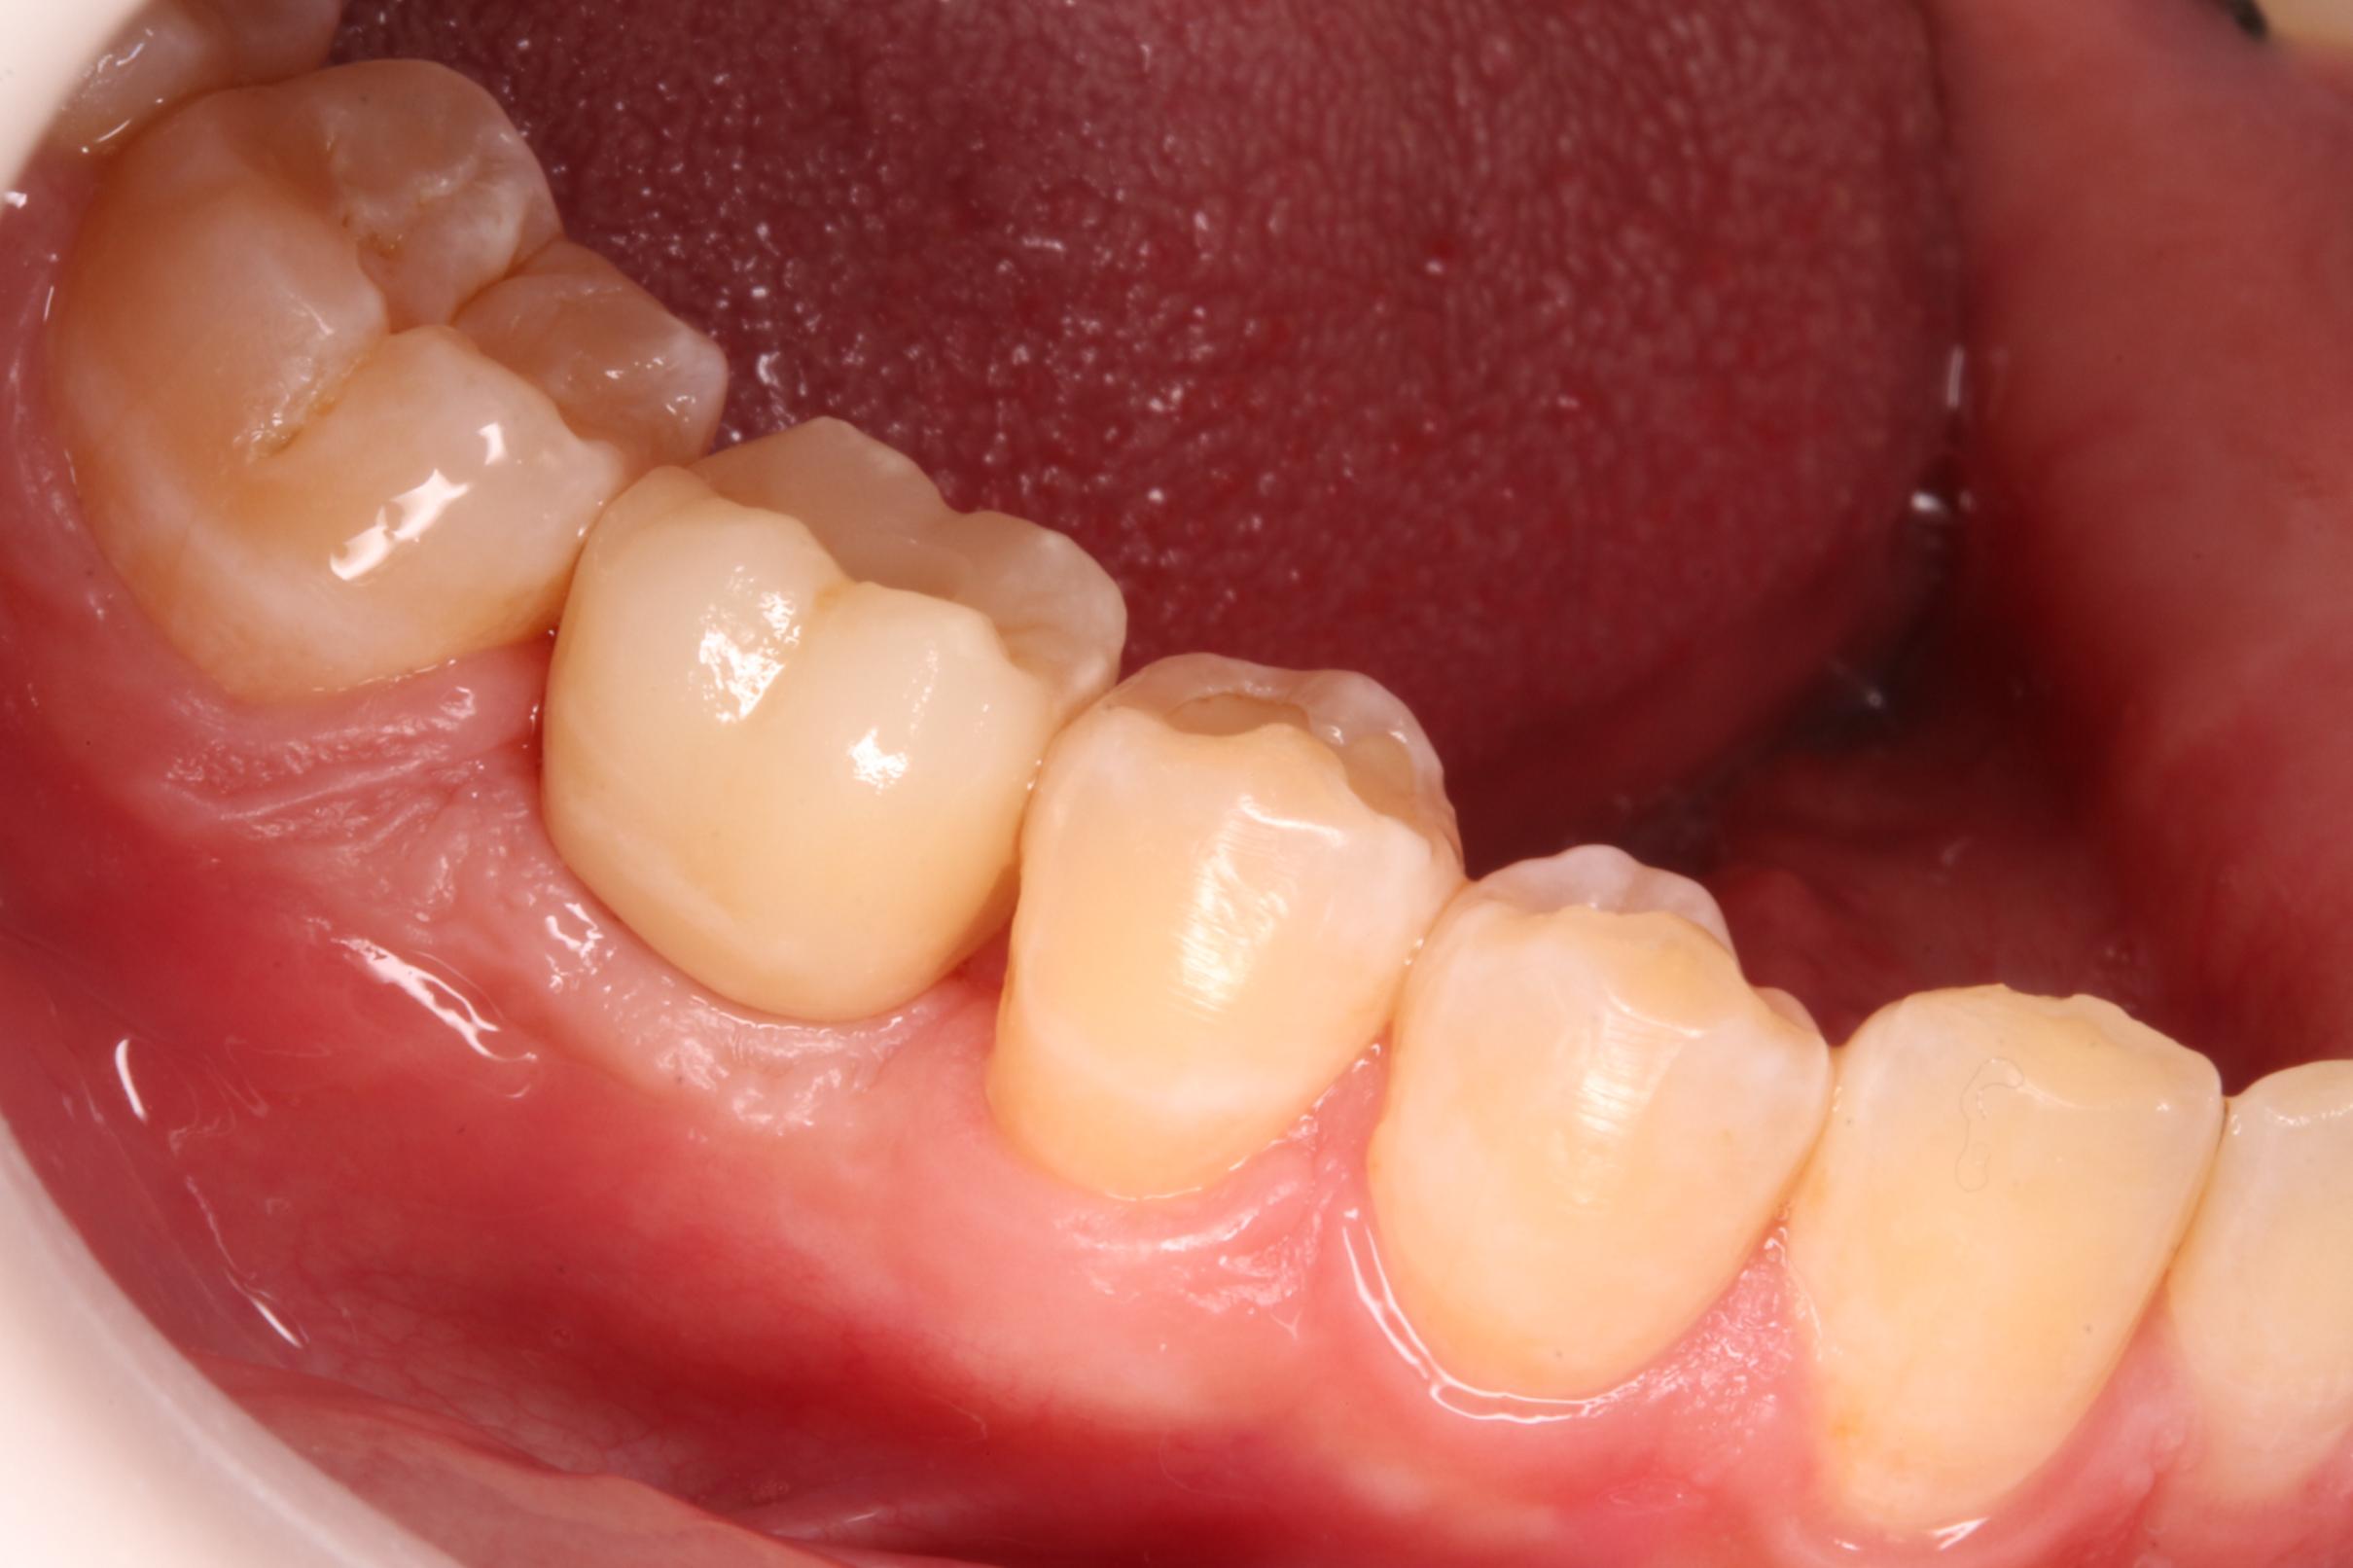

Implante y corona

Este paciente de 31 años acudió a la consulta porque había perdido una muela y deseaba rehabilitar su sonrisa. Nuestro cirujano colocó un implante dental en el espacio donde faltaba la pieza, y tras el tiempo necesario para que el implante se integrara correctamente al hueso, confeccionamos una corona en nuestro propio laboratorio. De esta manera, logramos devolverle tanto la función como la estética. El resultado fue tan natural que el paciente quedó encantado: la corona se mimetiza perfectamente con el resto de sus dientes, pasando completamente desapercibida.